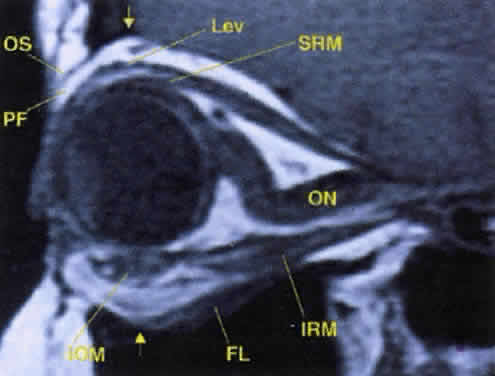

Fig. 17. The optic nerve (ON). A parasagittal MR image demonstrates the 7-mm excess of intraorbital

optic nerve, seen as an S shape. Also note the perpendicular relation

of the inferior oblique muscle (IOM) to the inferior rectus muscle (IRM). Other findings of anatomic interest in this image include the levator (Lev), the superior rectus muscle (SRM), the orbital septum (OS) arising from the arcus marginalis, and the preaponeurotic fat pad (PF) between the septum and the levator. Note that the orbital floor (FL) is angled upward by 15° to 20° from anterior to posterior. Fig. 17. The optic nerve (ON). A parasagittal MR image demonstrates the 7-mm excess of intraorbital

optic nerve, seen as an S shape. Also note the perpendicular relation

of the inferior oblique muscle (IOM) to the inferior rectus muscle (IRM). Other findings of anatomic interest in this image include the levator (Lev), the superior rectus muscle (SRM), the orbital septum (OS) arising from the arcus marginalis, and the preaponeurotic fat pad (PF) between the septum and the levator. Note that the orbital floor (FL) is angled upward by 15° to 20° from anterior to posterior.

|